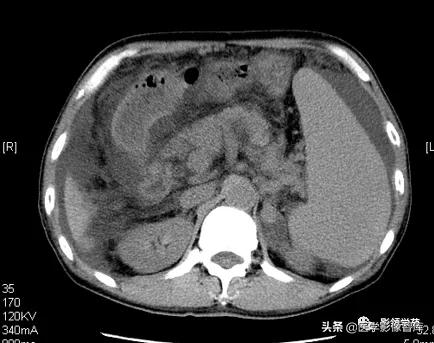

增强扫描:动脉期脾脏呈斑片状不均匀强化,静脉期及平衡期强化密度逐渐均匀。